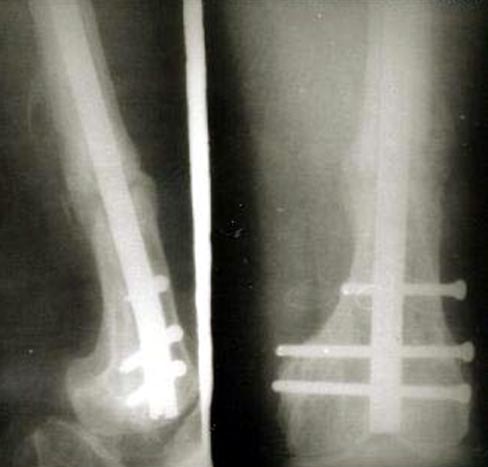

病例二、患者33岁,股骨髁上骨折骨不连2年,曾用Ender’s钉固定断端不稳定,抗旋转性不足,钉移位退出失去固定作用而失败。我们采用逆行髓内钉内固定,以及骨髓细胞复合生长因子植骨术,术后1年X线片连续性骨痂形成,膝关节功能良好。